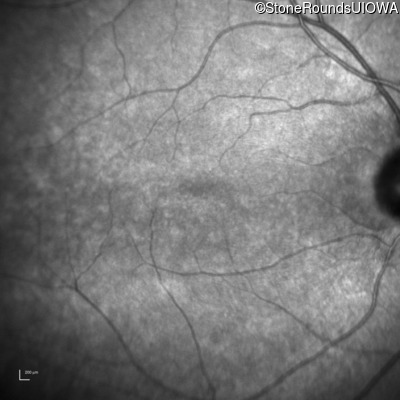

Congenital Stationary Synaptic Dysfunction (IA2g)

Congenital Stationary Synaptic Dysfunction (IA2g)

| Congenital Stationary Synaptic Dysfunction | CABP4 | Arg49Stop CGA>TGA | IVS1+1 G>T | AR |